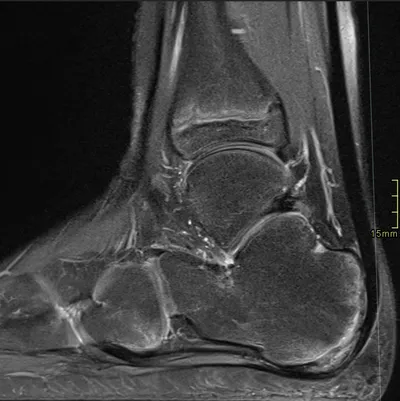

Apophysitis Radiology Images

Browse 3 medical images tagged with apophysitis. This collection includes various imaging modalities for medical education and reference.

About Apophysitis Imaging

- This collection contains 3 radiology images related to apophysitis, including various imaging modalities such as X-rays, MRIs, CT scans, and ultrasound images commonly used in medical diagnosis and education.